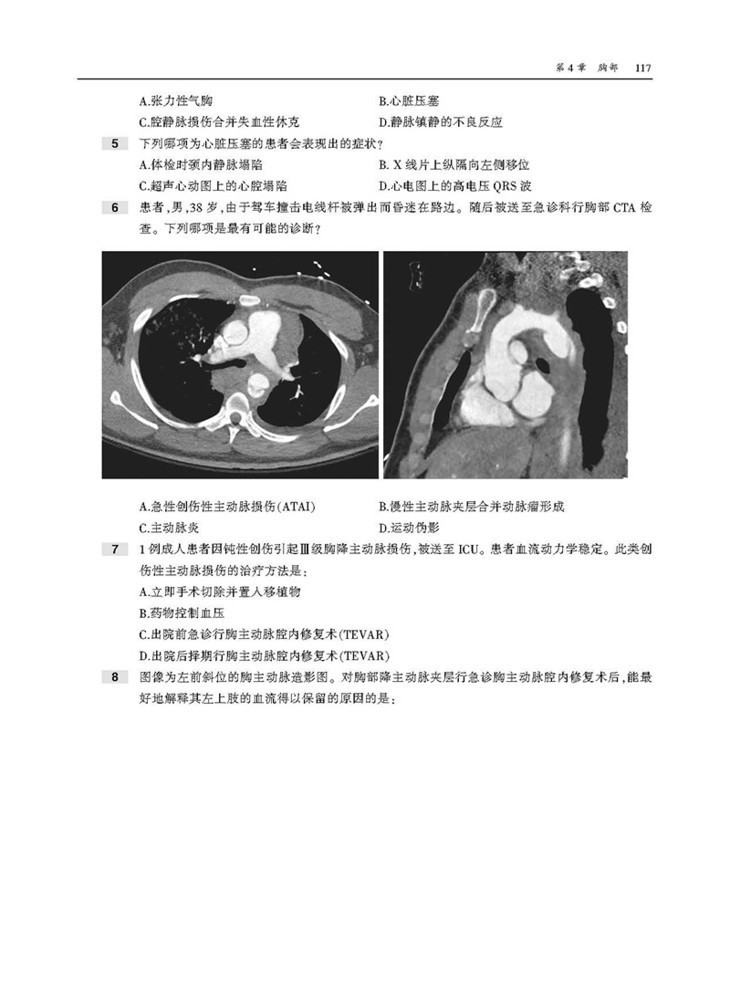

本书为“影像学核心复习系列丛书”之一,内容翔实,通过相关病例以及对应影像图,对血管介入放射学的内容进行了描述。本书囊括上百幅高清图像,直观展示病变要点。每章采取选择题形式,首先给出患者病史和影像图片,然后列出问题和选项,便于读者独立思考,选择答案。各章“答案与解析”部分不仅详细解释正确答案,而且说明错误选项的原因,此外,问题后还配有相关参考文献,有助于读者进一步扩展知识,有针对性地进行阅读和复习。

2. 直观性,本书按部位分别论述了胸部、胃肠道系统、泌尿系统、生殖内分泌系统的介入治疗,含百余幅高清图像,直观展示病变要点,是临床医师迫切需要并且手头缺乏的重要参考资料。